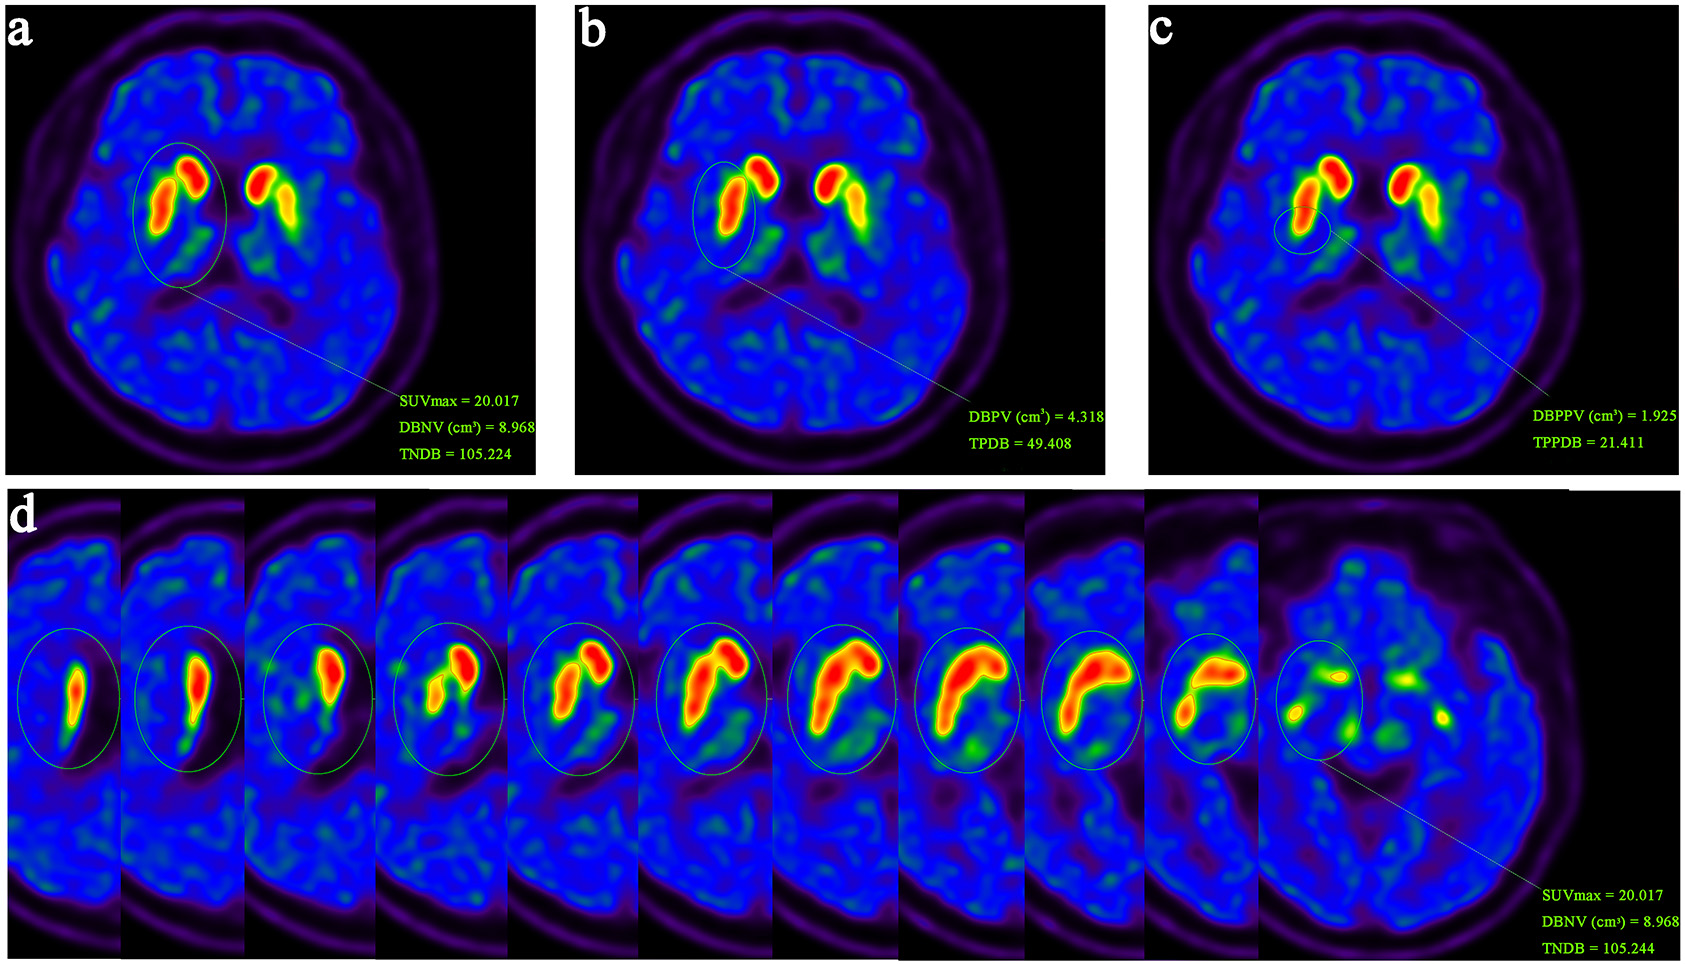

A total of 75 patients with PD who underwent 11C-methyl-N-2β-methyl ester-3β-(4-fluorophenyl) tropane (11C-CFT) PET/CT from April, 2019 to June, 2021 were retrospectively analyzed. Clinical characteristics, including age, sex, and disease duration, as well as the modified Hoehn-Yahr (H-Y) scale, Unified Parkinson’s Disease Rating Scale (UPDRS) parts II and III (II-III), and Mini-Mental State Examination (MMSE) scores of PD patients during the corresponding time periods were collected. DAT binding parameters and their derived parameters based on plane and 3D images in the neostriatum were analyzed for consistency with plane and 3D parameters, and the correlation between DAT parameters and the clinical features of patients were assessed using SPSS software.

The DAT binding parameters derived from 3D images demonstrated good consistency with the plane parameters (p < 0.05). The asymmetry index (ai) of DAT binding parameters based on 3D and plane images showed good consistency in the anterior putamen (p < 0.05). The plane parameters of the anterior and posterior putamen were statistically correlated with the UPDRS II-III score and H-Y score of PD patients (p < 0.05), whereas those of the caudate nucleus were correlated with UPDRS II and MMSE scores. The 3D parameters in the neostriatum showed good statistical correlation with disease duration, UPDRS II-III score, H-Y score, and H-Y stage of PD patients (p < 0.05), and the ai was significantly correlated with MMSE score (p < 0.05). The 3D parameters in the putamen and posterior putamen exhibited significant statistical correlation with the UPDRS II-III score, H-Y score, and H-Y stage in PD patients (p < 0.05). The ai in the putamen showed statistical correlation with UPDRS III and MMSE scores, and the ai in the posterior putamen showed statistical correlation with UPDRS II score (p < 0.05).

Quantitative parameters based on plane and 3D images of 11C-CFT PET/CT showed good consistency. Moreover, 3D parameters in the neostriatum had a stronger correlation with activities of daily living, UPDRS motor scores, disease severity and duration, and cognition compared with plane parameters in PD patients.